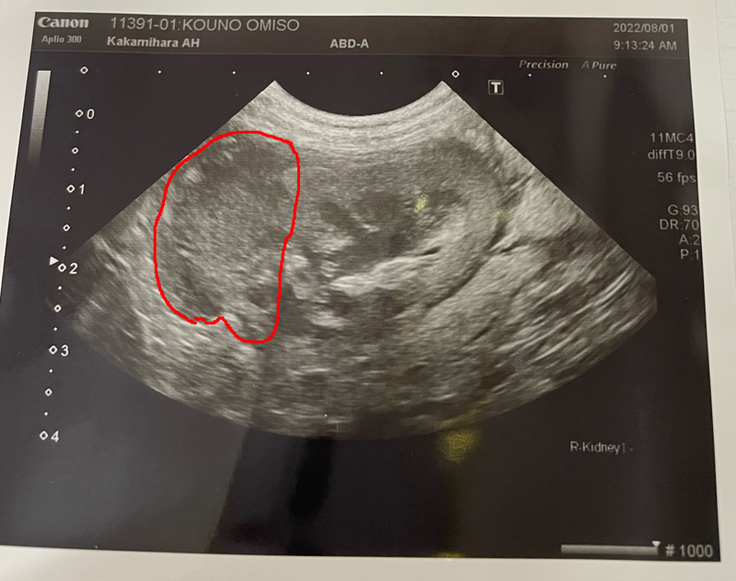

エコー画像では、やはり2週間ほど治療が出来なかったので、腫瘍の増大が見られました。とは言え、現在は初期の状態よりは小さいのですが。

新たに今回、若干大きくなった腫瘍が腎臓壁を圧迫するようになり、腎臓と外側の膜の間に出血がみられました。出血の程度は大きくなかったようでしたので心配は無いみたいです。